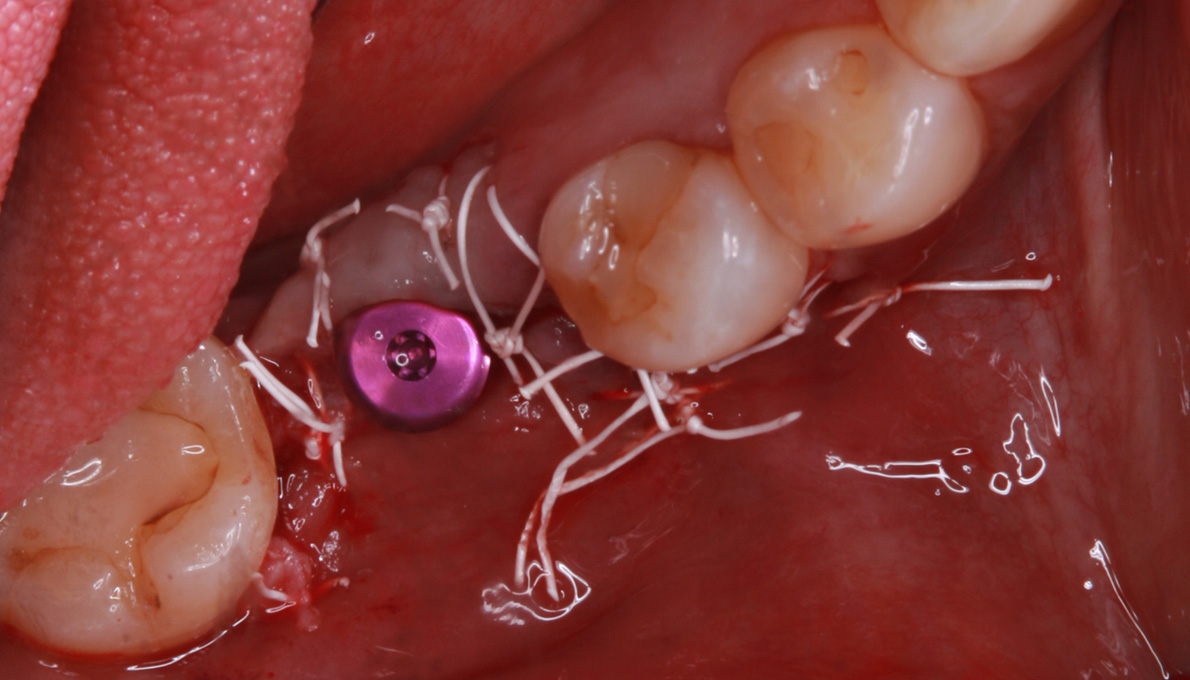

インプラント手術を行いました。

手術の時に使用するサージカルステント

レントゲン画像 -